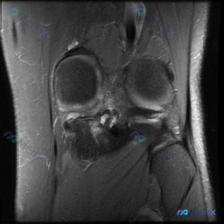

今天整理一份很有代表性的膝关节MRI读片病例,和大家分享一下思路。这个病例最初是被怀疑有半月板异常,我们一起来看看实际情况。 病例影像基本信息 这是一份膝关节MRI冠状位T2加权图像,我们先梳理所有基础观察: 1. 股骨远端、胫骨近端骨髓信号正常,没有明显骨髓水肿 2. 半月板情况:内侧半月板体部形...